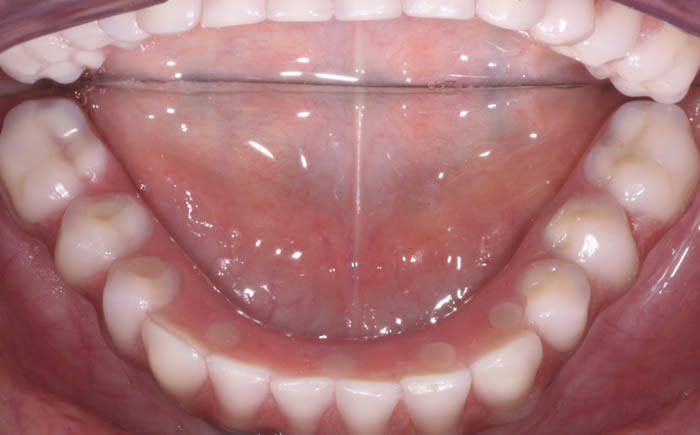

Case One (5 images)

Full set of lower teeth fixed onto five dental implants.

Case Two (8 images)